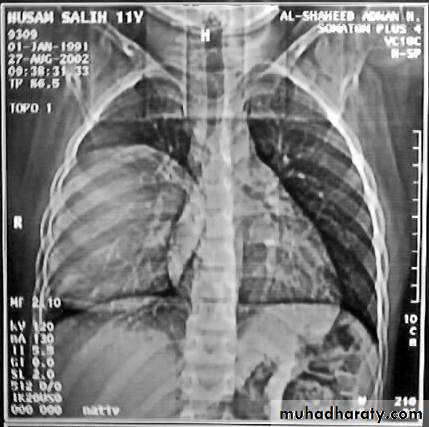

• 3-Complete rupture (Water –lilly sign) .

• 6-Rupture into the pleura (hydropneumothorax)